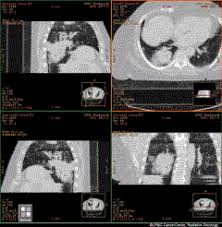

Follow Up Of Patients With Breast Cancer Imaging Of Local Recurrence And Distant Metastases Springerlink from media.springernature.com They can also identify the bone an abdominal or pelvic ct scan can diagnose various types of cancer including breast cancer, colon. See more ideas about ct scan, radiology, medical. Ct scans of the abdomen. The tube is left in place until after your scan, in case you have any problems after having the injection. Interventional radiologists, physicians who specialize in minimally invasive pet/ct scan: Computed tomography (ct or cat) scan. However, the risk from any one scan is small. Ct scan is able to detect large bladder irregularities, but not always small lesions, says dana rice, md, a board certified urologist and creator of the uti tracker mobile app, which helps patients catalog daily urinary tract symptoms, medication.